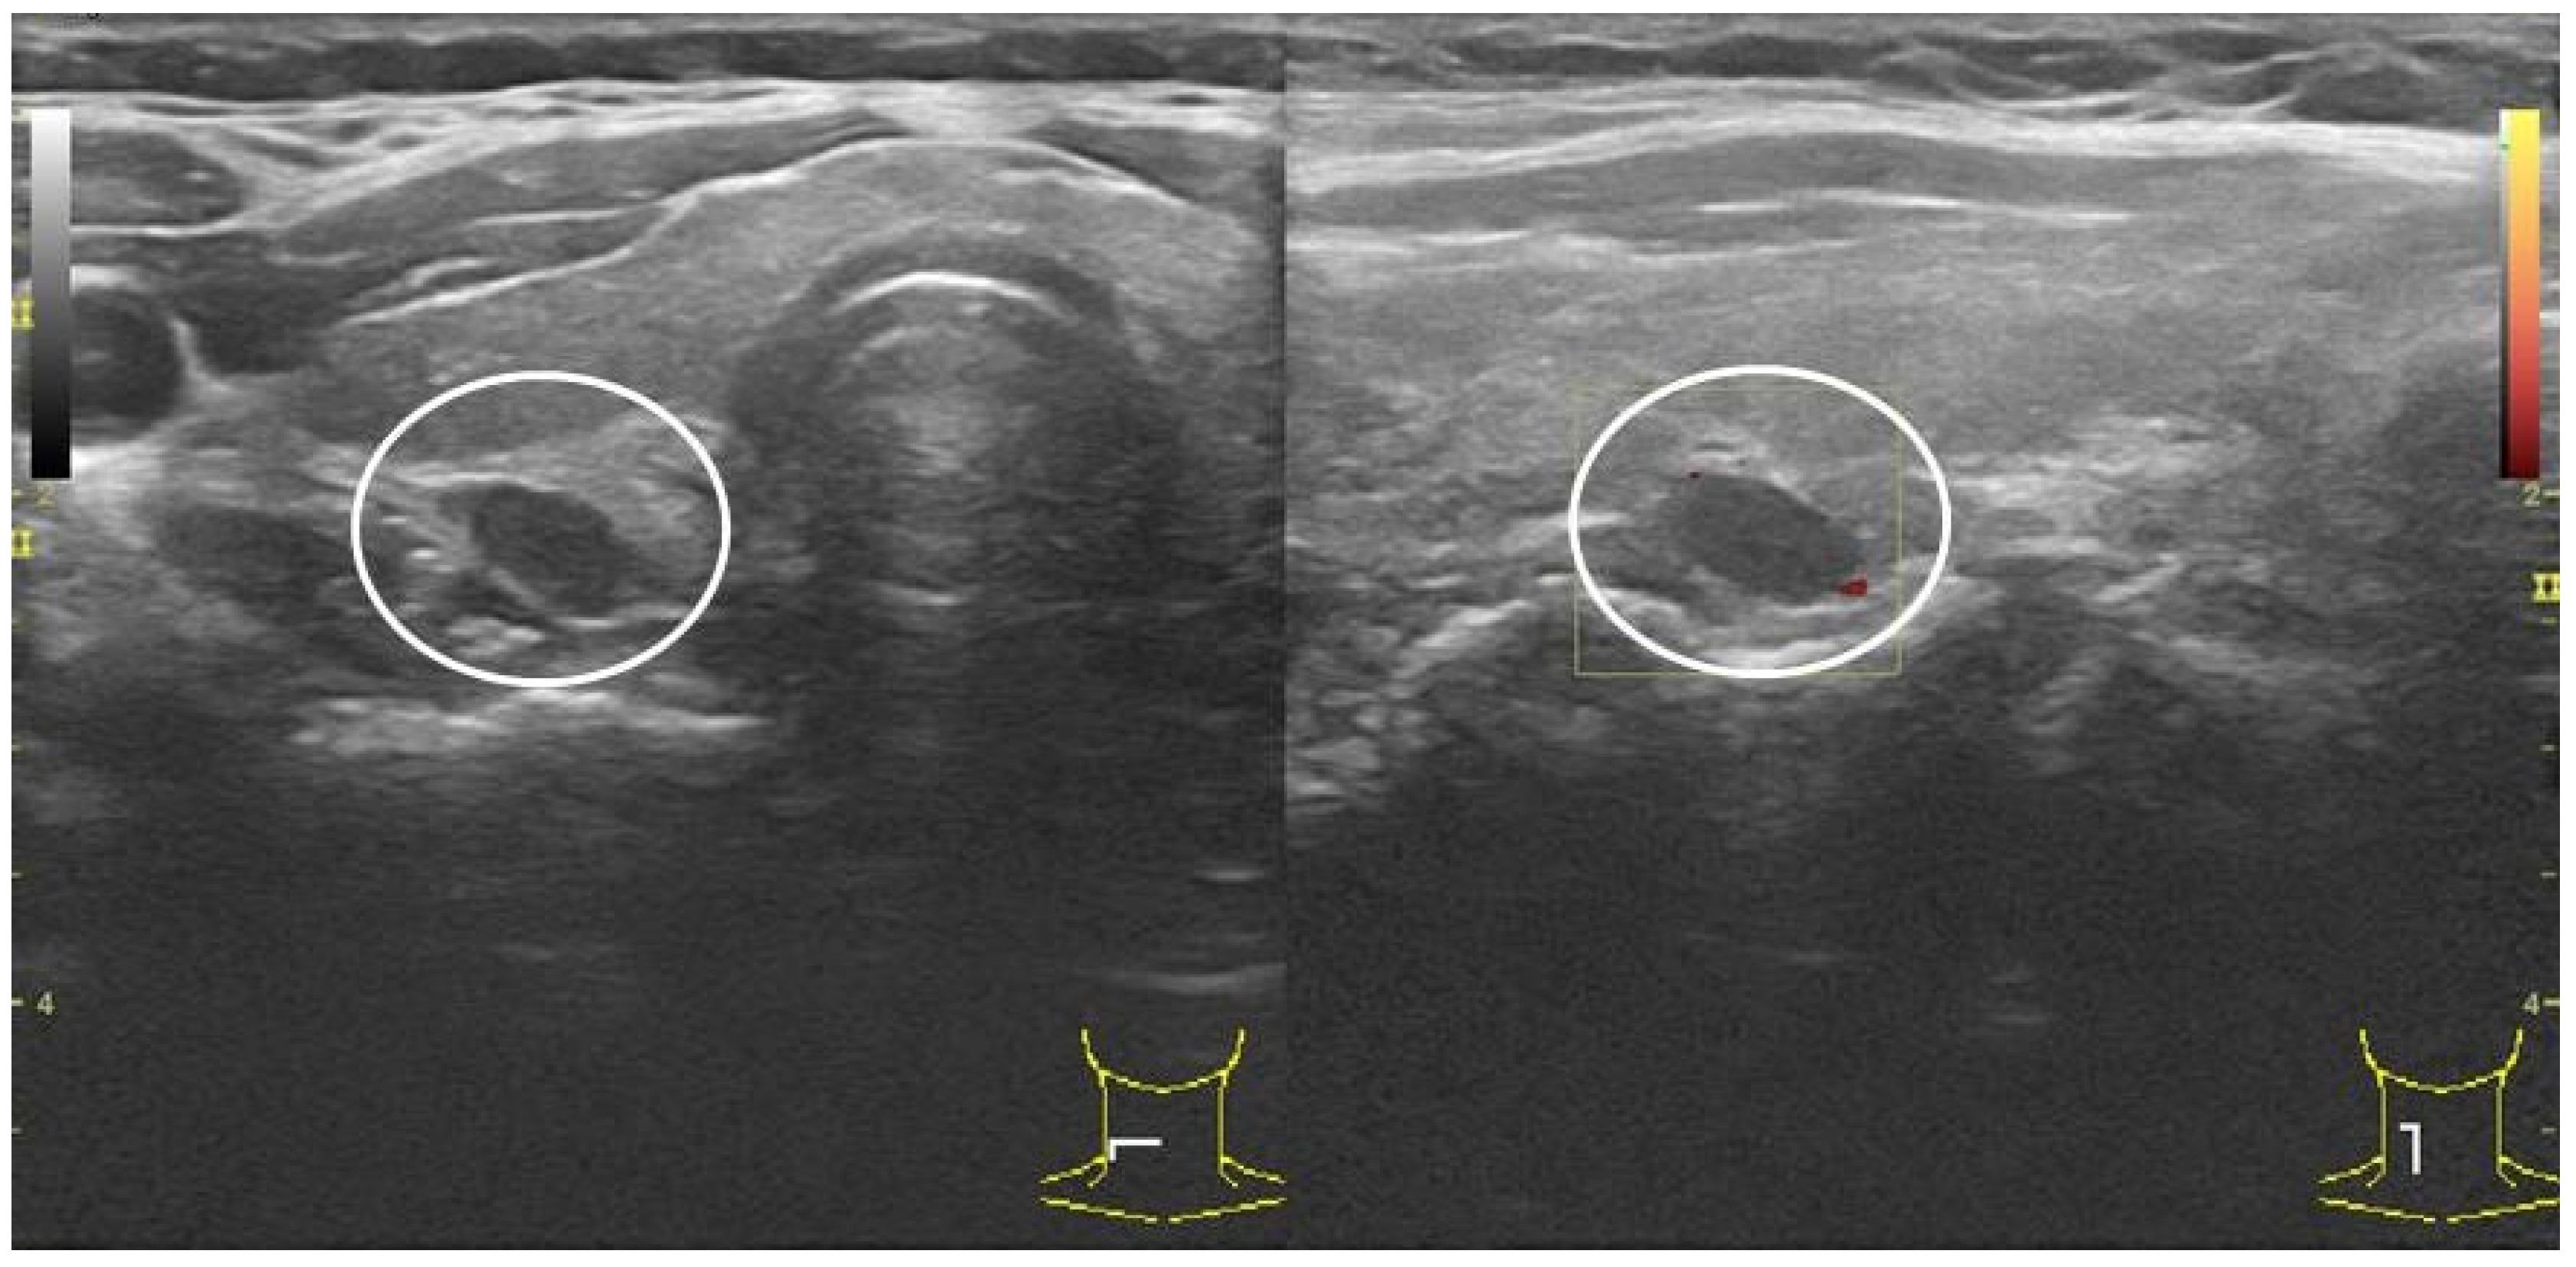

2.4. P-FNAB Procedure

- Visualization of the tip of the needle in PG according to authors’ own scale, QuOBo (Quality of Biopsy; see below for details);

- USG control directly after P-FNAB and 15–30 min later.